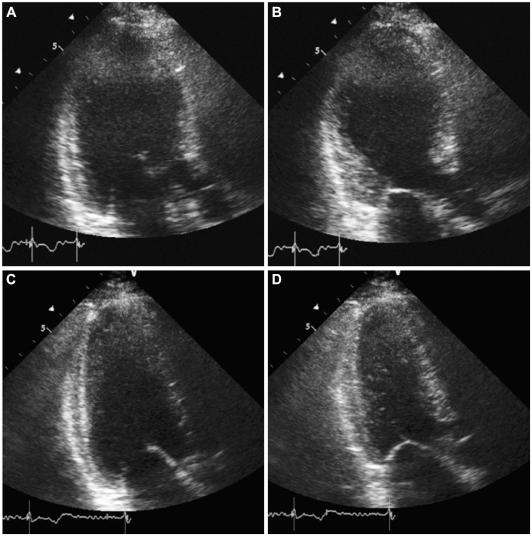

Takotsubo cardiomyopathy typically affects post-menopausal women who experience severe psychological or physical stress. It can also develop after medical procedures or surgery. Although the underlying mechanism has not been clearly elucidated, catecholamine overload is one of the most plausible etiologies. Herein we report a case of takotsubo-like left ventricular (LV) dysfunction in a 28-year old woman who underwent Cesarean delivery. She presented with acute heart failure and pulmonary edema immediately after the delivery. Her echocardiography showed severe LV dysfunction and apical ballooning. This case is clinically and pathophysiologically similar to peripartum cardiomyopathy.

应激性心肌病通常影响绝经后经历严重心理或身体应激的女性。它也可能在医疗程序或手术后发展。尽管其潜在机制尚未明确阐明,但儿茶酚胺过载是最合理的病因之一。本文报告了一例 28 岁行剖宫产术的女性发生类似应激性心肌病的左心室(LV)功能障碍。她在分娩后立即出现急性心力衰竭和肺水肿。她的超声心动图显示严重的 LV 功能障碍和心尖球囊样变。该病例在临床表现和病理生理学上与围产期心肌病相似。